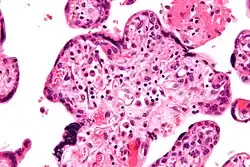

VUE does not have specific clinical signs and symptoms suggesting diagnosis; but an analysis of the inflammatory filtrate can aid in diagnosis.[1] The composition of inflammatory infiltrate in VUE on a cellular level is primarily macrophages and lymphocytes. The relative proportions of cells vary case by case. The lymphocytes present in VUE are predominantly CD8+ T-cells then CD4. There is usually a ratio of 0.1 to 0.5 for CD4/CD8.[17][18] The macrophages present are mainly Mac387-, followed by CD68 and HAM56+. Class 2 major histocompatibility complex (MHC) antigens on macrophages are up-regulated at sites of VUE. Neutrophils should not be present at sites of VUE. VUE is a condition involving inflammation and not infection. High numbers of neutrophils are present in infectious villitis and not VUE.[1][14]

Histomorphologically, VUE is characterized by a lymphocytic infiltrate of the chorionic villi without a demonstrable cause. Plasma cells should be absent; the presence of plasma cells suggests an infective etiology, e.g. CMV infection.

Intermed. mag.

High mag.